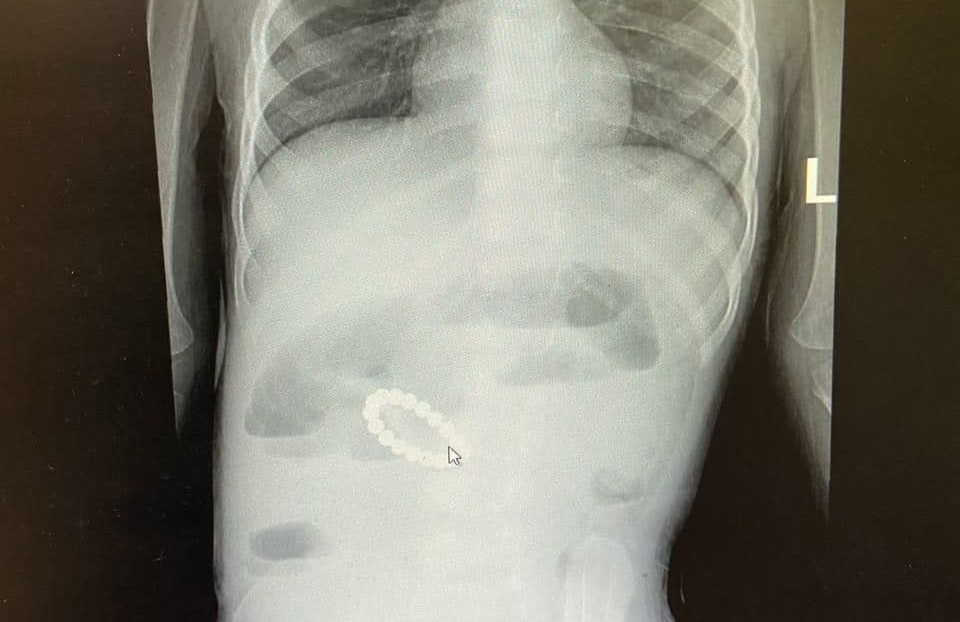

ок проглотил кольцо

Ребенок проглотил кольцо 116 фото